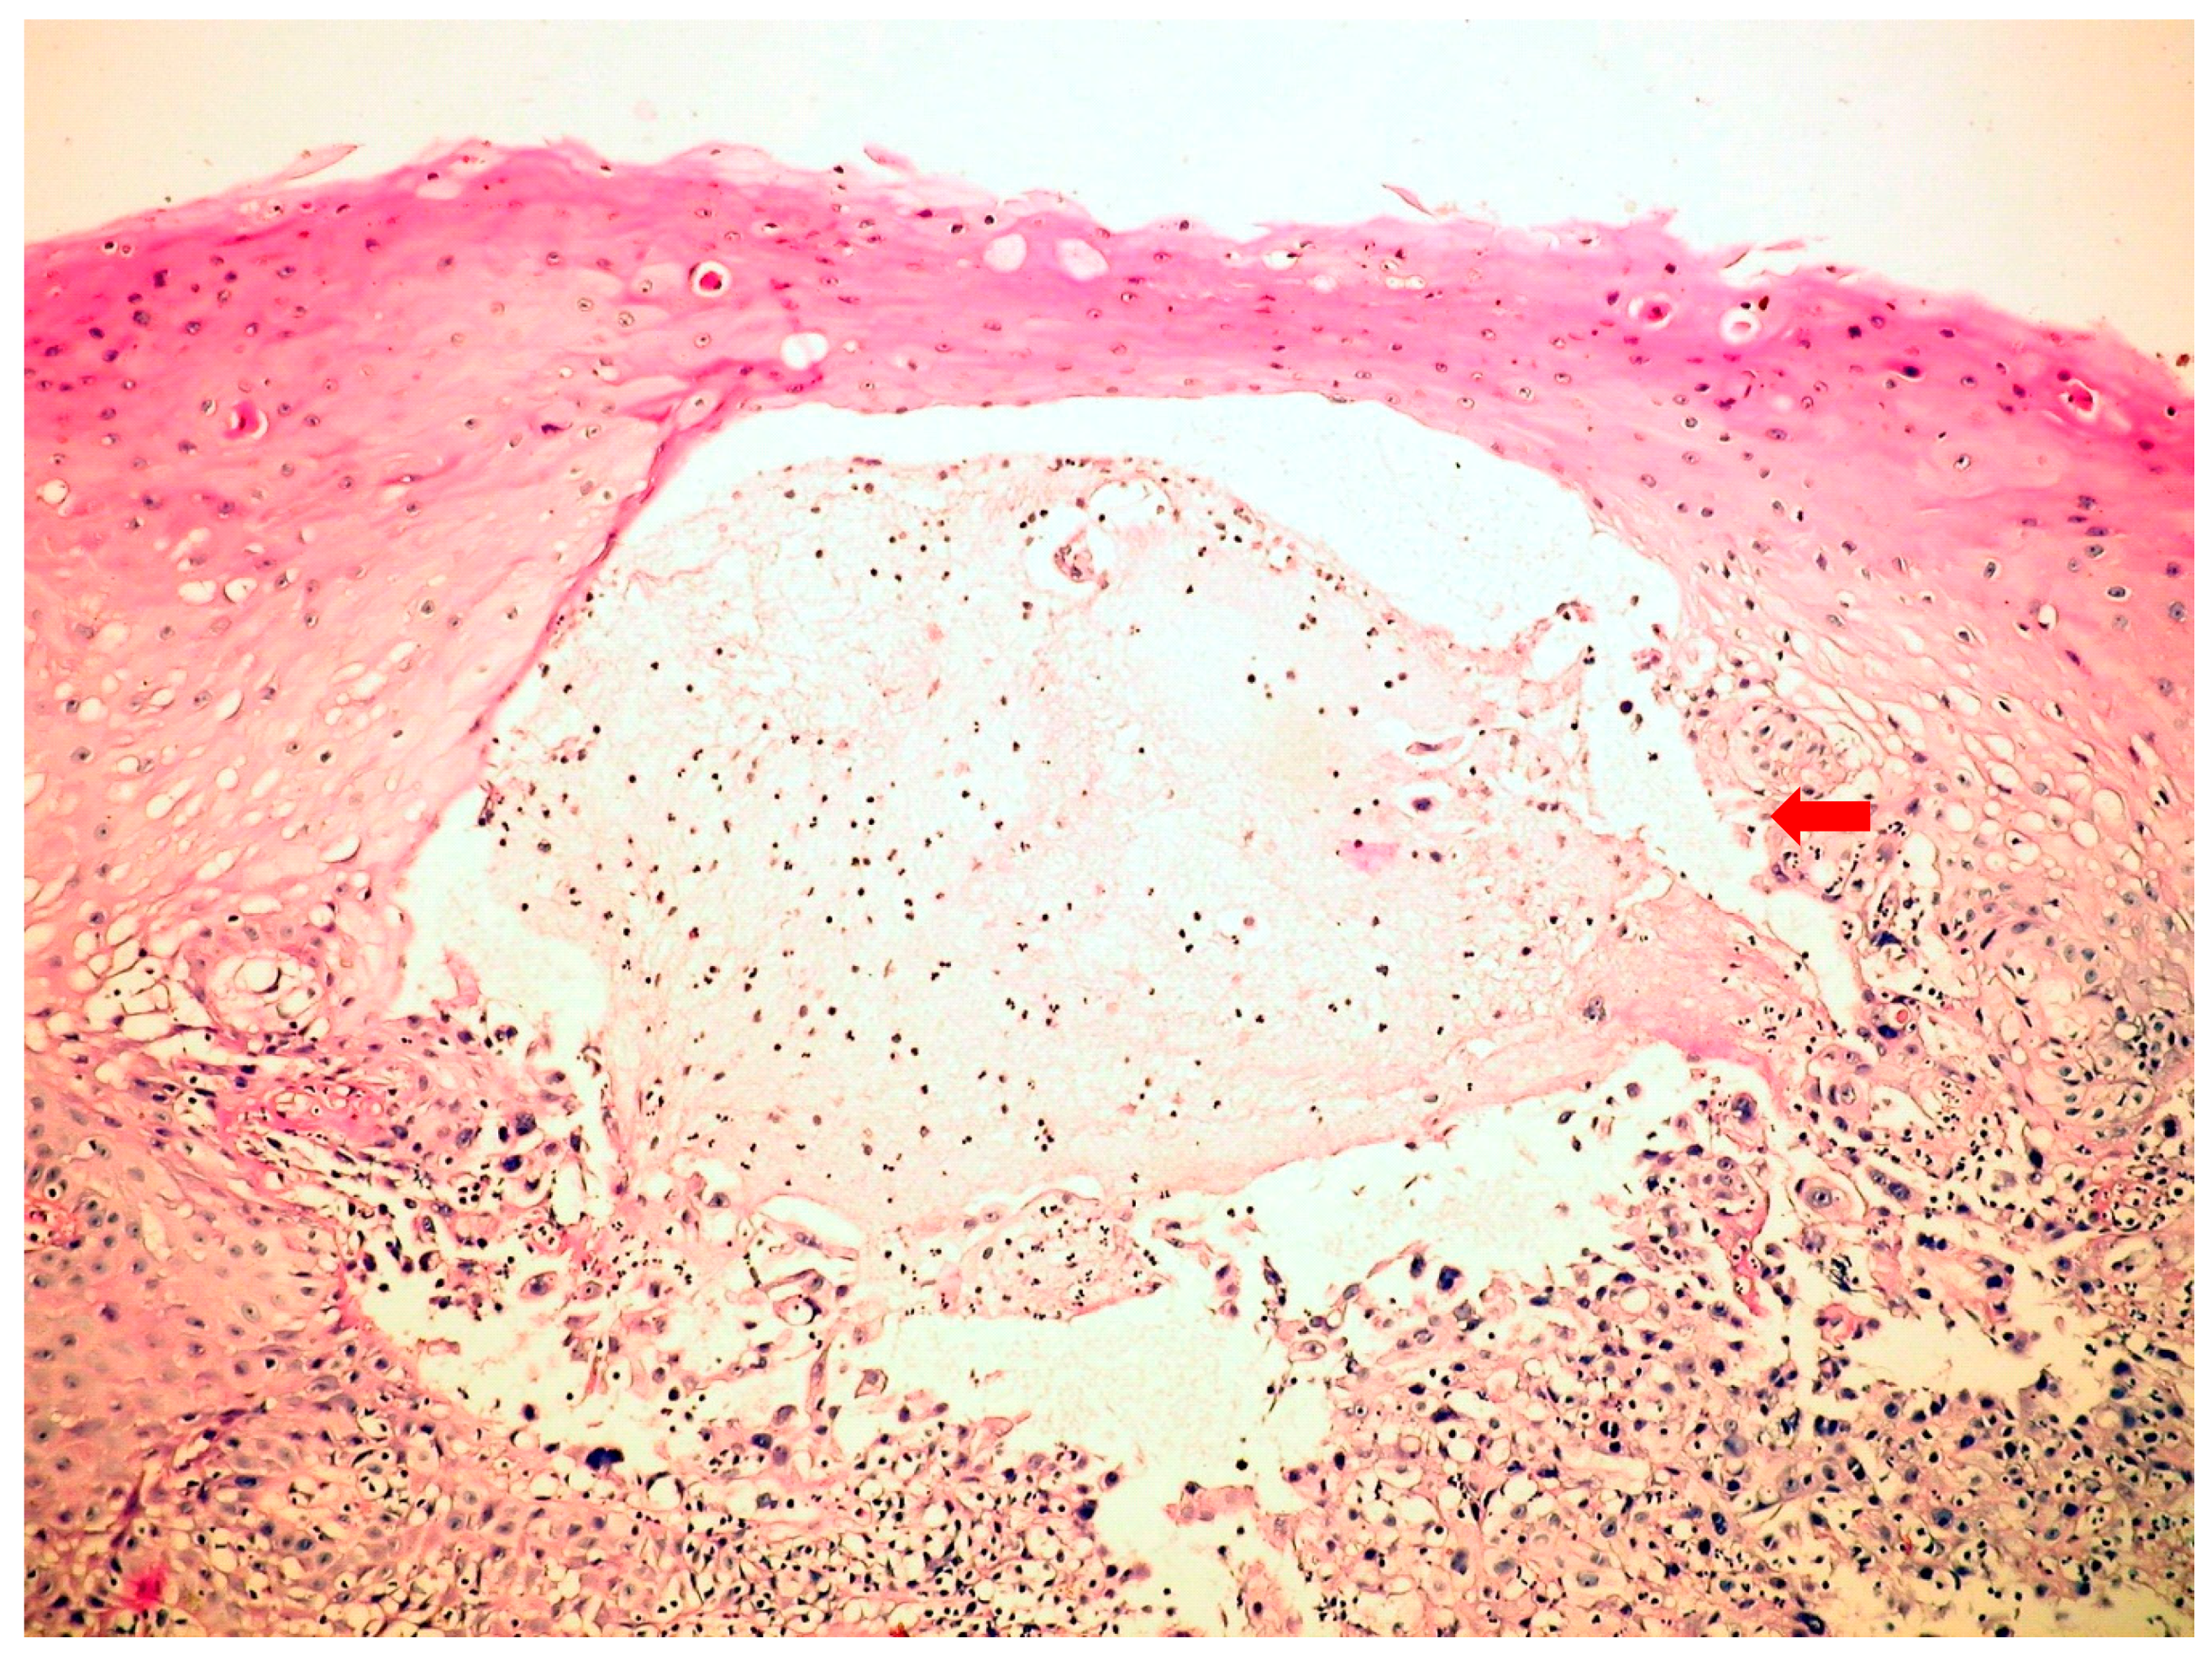

The endoscopic features were quite characteristic. Upper gastrointestinal endoscopy in C.albicans esophagitis revealed multiple, elevated, adherent, and confluent white plaques localized in the upper, mid, and lower esophagus. The esophageal mucosa had a friable and erythematous appearance. Stomach and duodenum were normal. To confirm diagnosis, biopsies were performed, showing the presence of yeasts and pseudohyphae into mucosal cells. Microbiologic cultures of brushings obtained from the esophagus were positive for C.albicans. Esophagogastroduodenoscopy in HSV esophagitis showed multiple, superficial, small, well-circumscribed, vesicular “punched-out” ulcers with acute inflammation and normal intervening mucosa, starting from the mid and extending to lower esophagus. In patients with post-mortem-diagnosed IE, lesions were spread throughout the entire esophagus. Biopsies taken from the edge of these ulcers revealed typical cytopathic epithelial changes, including multinucleated giant cells and intranuclear eosinophilic inclusion bodies. Cytological examination of the esophageal biopsy specimens showed an ulcerated esophageal mucosa (Figure 1) with acute inflammation and intranuclear and intracytoplasmic characteristics inclusion bodies (Cowdry type A). Esophagogastroduodenoscopy in CMV esophagitis revealed a single, large, and deep ulcer, located in the middle section of the esophagus. A severe form of esophagitis with increased friability was also found in this kind of infection. Cytology smears from esophageal brushings revealed an ulcerated esophageal mucosa with acute inflammation and intracytoplasmic and intranuclear large (Figure 2), basophilic inclusion bodies (PAS +) surrounded by a clear halo (Cowdry type B). Antifungal therapy with Fluconazole was initiated in C.albicans-induced esophagitis patients, and, within two weeks after starting therapy, symptoms were reduced. Acyclovir therapy was used in HSV-induced esophagitis patients, while Ganciclovir was required for treatment in CMV-induced esophagitis patients. A second endoscopy at the end of the fungal or viral treatment was not performed.

Figure 1. Herpes simplex virus (HSV)-inducedesophagitis (microscopy-HE, 400×) with serous vesicle formation.